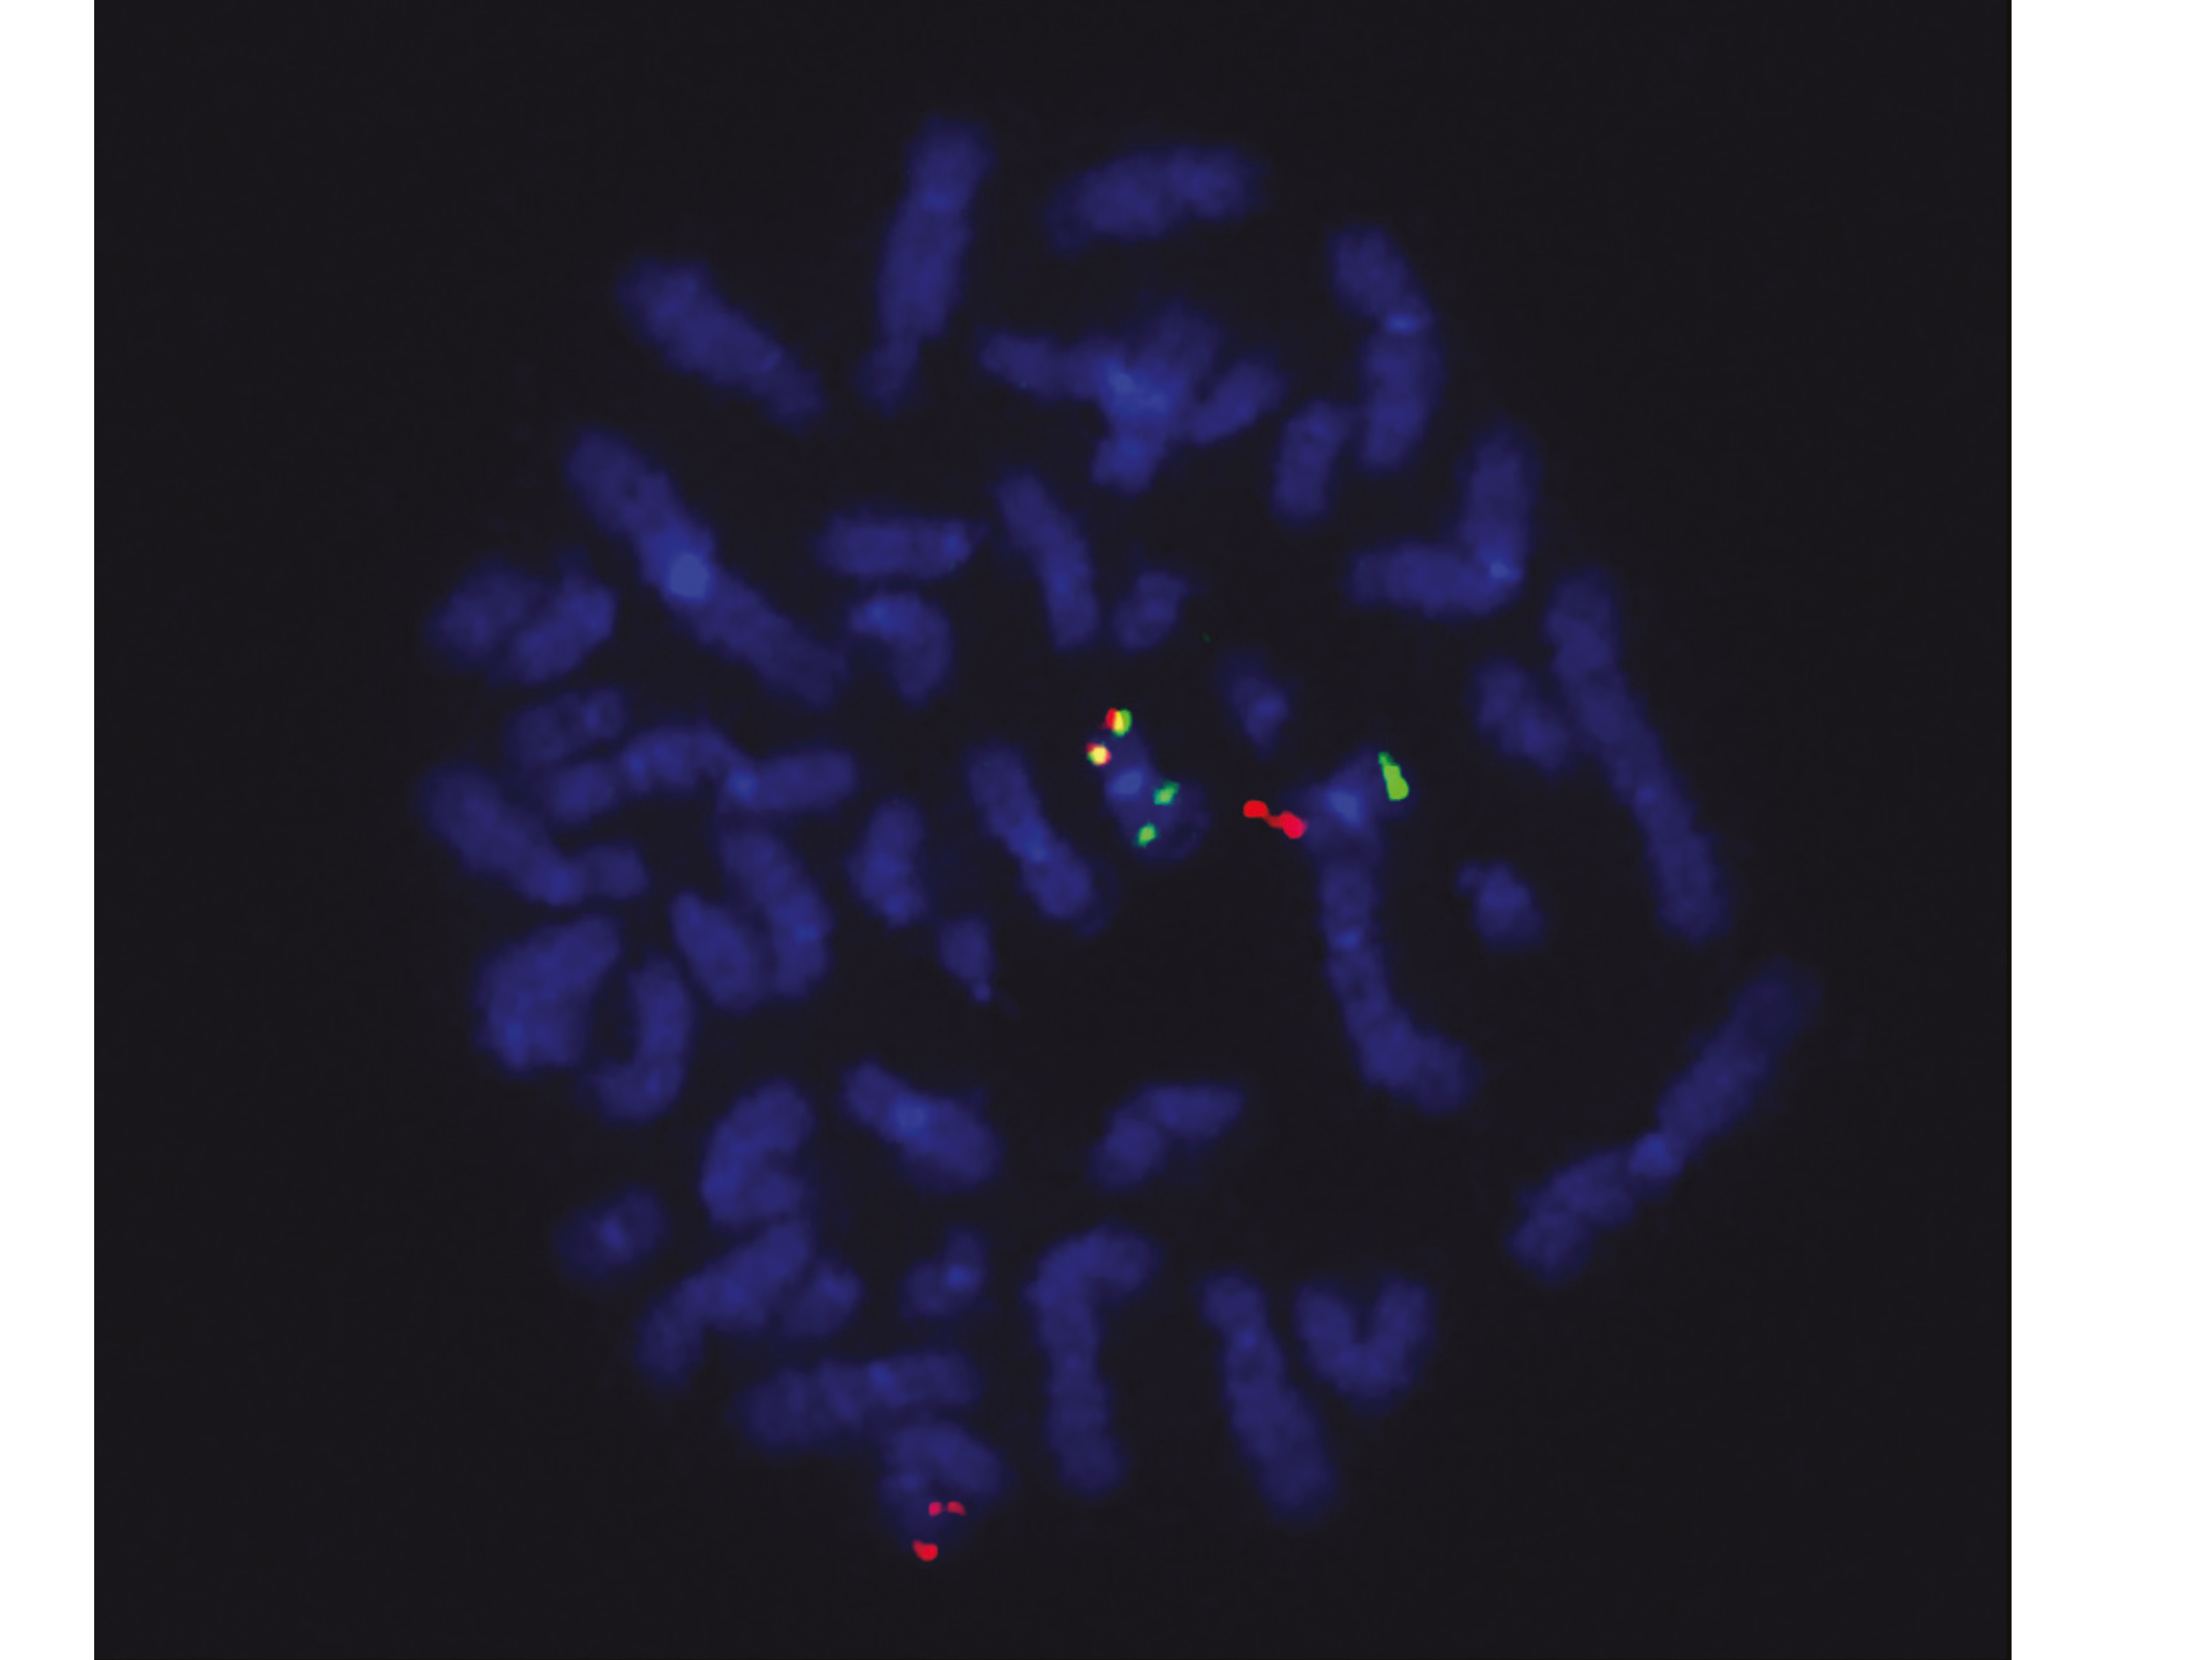

2012 fanden die Forschenden um Mercher dass die Krankheit AML-M7 bei Kindern häufig genetische Veränderungen aufweist, die zur Expression eines abnormen Proteins führen. Dieses entsteht durch die Fusion von zwei normalerweise unabhängigen Genen in der Zelle. Obwohl diese Fusion – bekannt als ETO2-GLIS2 – in 30 % der Fälle von AML-M7 identifiziert wurde, konnten die Forschenden diese Anomalie bisher nicht erklären. Ebenso unklar war bisher, warum Kinder mit AML-M7 und diesem Fusionsgen meist jünger als zwei Jahre alt sind, während ältere Kinder mit dieser Veränderung meist an einer anderen AML-Form leiden.

Um diese Fragen zu beantworten, entwickelten die Forschenden ein Mausmodell von AML-M7 mit einer ETO2-GLIS2-Fusion. Mit diesem Modell konnten die Forscher erstmals zeigen, dass sich bei einer Aktivierung der ETO2-GLIS2-Fusion in Zellen der fötalen Blutbildung sehr rasch eine aggressive Leukämie entwickelte – die der AML-M7 beim Kind sehr ähnlich ist. Wurde dagegen die Fusion in Blutbildungszellen von erwachsenen Tieren aktiviert, trat diese typische kindliche Leukämie nicht auf, während sich andere AML-Formen erst viel später entwickelten. Wenn die Forschenden die Ausbildung der ETO2-GLIS2-Fusion unterbrachen, konnten sich die zuvor leukämischen Zellen wieder in normale Blutzellen ausdifferenzieren.

Diese Beobachtungen weisen darauf hin, dass diese Leukämie deshalb nur bei Kleinkindern auftritt, weil die fötalen Blutbildungszellen – anders als die erwachsenen – eine höhere Empfindlichkeit für bestimmte genetische Mutationen wie die ETO2-GLIS2-Fusion besitzen. Die Studie zeigt auch, dass die ETO2-GLIS2-Fusion der eigentliche Motor dieser kindlichen Leukämieform bildet. Die Forschenden werden nun versuchen, die Aktivität dieser Fusion in den Tumorzellen gezielt zu unterbrechen.